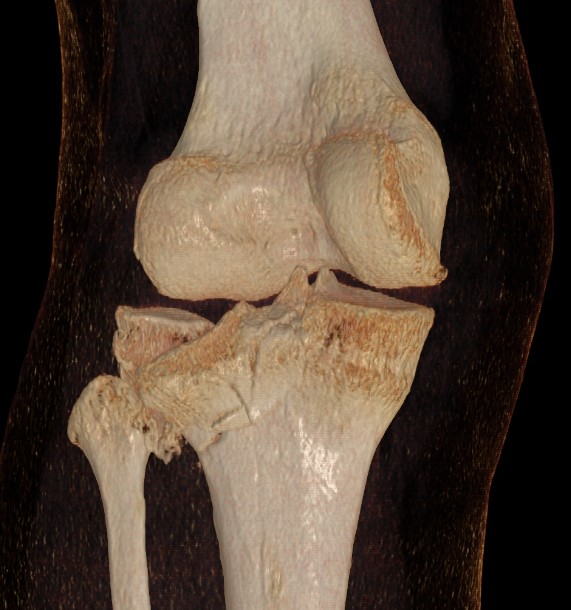

3 column concept of tibial plateau fractures

Luo et al. Orthop Trauma 2010

- introduces the 3 column concept

- medial column / lateral column / posterior column

- posterior column can be splint into medial and lateral fragments (posterolateral / posteromedial)

- imporant as any surgery must address these fragments

- typically require additional posteromedial or posterolateral approaches